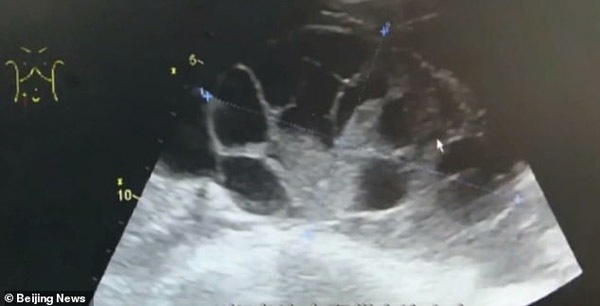

Ba ngày sau khi phẫu thuật, sức khỏe nữ sinh nhanh chóng xấu đi, cô bị đầy hơi nghiêm trọng, khó thở và nhanh chóng được đưa đến bệnh viện. Qua kết quả kiểm tra, nữ sinh được chẩn đoán mắc hội chứng quá kích buồng trứng, một tình trạng xảy ra khi buồng trứng trở nên quá kích thích do sự phát triển của trứng và chất lỏng tích tụ xung quanh.

Sau phẫu thuật hút trứng ra ngoài, buồng trứng của cô gái đã bị mở rộng như thể mang thai 7-8 tháng.

Cô gái trẻ được cho là đã tiêm hơn 10 mũi kích thích rụng trứng trước khi phẫu thuật lấy trứng. Các bác sĩ tiết lộ rằng hơn 5 lít chất lỏng đã được rút ra từ bụng của cô. Rõ ràng, buồng trứng của cô đã bị mở rộng như thể mang thai 7-8 tháng.